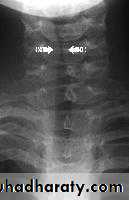

Anteroposterior X-ray of the neck shows subglottic narrowing (steeple sign).

Lateral X-ray of the neck may show swollen epiglottis (thumb sign).

Steeple sign (Croup) Thumb sign (Epiglottitis)